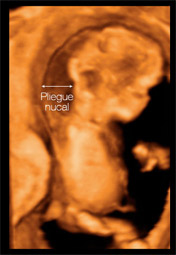

La ecografía mide el llamado pliegue nucal

Es una prueba fundamental. En primer lugar, le dicen si lo que espera es uno o dos bebés, si su crecimiento es el correcto y además le medirán la translucencia nucal (TN) o pliegue nucal: un acúmulo temporal de líquido en la región de la nuca del feto, como consecuencia del normal desarrollo linfático.

Qué significa el grosor del pliegue nucal

El incremento en el grosor del pliegue se ha relacionado con una amplia variedad de anomalías cromosómicas, como el síndrome de Down, el de Patau, el de Edwards, y el de Turner, y defectos anatómicos, como las cardiopatías. Aunque los datos varían en los distintos estudios se considera que una translucencia nucal por encima de los 2,5 mm o 3 mm no es un buen dato, y de hecho en un 77 por ciento de los casos se confirma que hay algún problema, aunque también hay un 4,7 por ciento de falsos positivos. Es decir, niños que presentan una translucencia nucal aumentada, pero eran sanos.

O al revés: fetos que tenían una translucencia normal nacieron con problemas. Por eso no se puede utilizar para diagnosticar problemas cromosómicos. También observarán otros signos que puedan hacer sospechar al médico que algo no va bien como la ausencia de hueso nasal en examen ecográfico.

"En esta ecografía valoramos el número de embriones, se realiza un estudio morfológico básico, se descarta la presencia de malformaciones cromosómicas midiendo la translucencia [o pliegue] nucal y otros parámetros y se hace una valoración de factores de riesgo que pueden predisponer a padecer enfermedades específicas del embarazo, como la preeclampsia".

“El incremento del tamaño de la nuca tiene relación con el síndrome de Down y otras alteraciones como malformaciones cardiacas”.

Dr. Fernando Gil Raga, Jefe del Servicio de Ginecología y Obstetricia del Hospital de Manises.